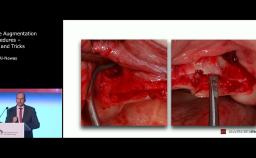

Following extraction, the tooth socket undergoes a healing process and series of changes, which include remodeling of the bone and alteration of the alveolar ridge dimensions. Management of the extraction socket can be challenging, especially in the esthetic zone. It has been documented that within 12 months of tooth extraction an average of 50% of resorption of the alveolar ridge can be expected to occur. Recently, an increasing body of evidence has reported that a substantial number of subjects from the Asian population demonstrated increased tooth-root-to-alveolus angulation. These data suggest that an impact from the management of the extraction socket defect and the implant placement timing must be considered due to an anatomic variation from the Caucasian population.

The lecture will review the relevant anatomic and surgical considerations in the Asian population. In addition, different regenerative techniques will be discussed to improve peri-implant soft and hard tissue defects.